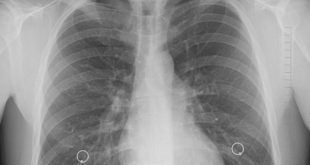

En México se han detectado alrededor de cuatro mil casos de hipertensión arterial pulmonar, enfermedad que afecta al corazón y los pulmones y cuyo blanco predilecto son las mujeres en etapa reproductiva. De acuerdo con el Instituto Nacional de Cancerología tres de cada cuatro casos se presentan en mujeres de …